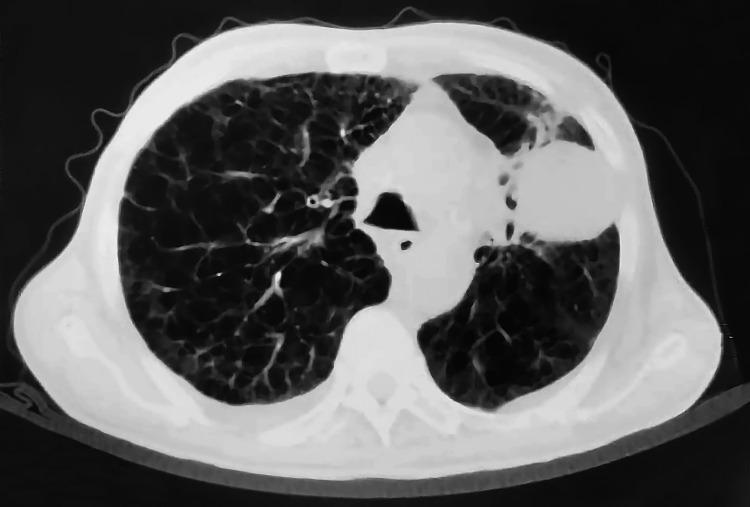

我们报告了沙特阿拉伯首例通过逆转录-聚合酶链反应技术证实存在 Kirsten 大鼠肉瘤病毒癌基因同源物(KRAS)G12C 突变的两例肺腺癌患者的病例系列。两名患者均为男性,年龄分别为 64 岁和 76 岁。第一名患者有重度吸烟史,而第二名患者未报告任何吸烟史。两例患者的肿瘤亚型均被确定为非黏液性肺腺癌。较年轻的患者表现为全身淋巴结肿大和右侧肺部肿块病变,而较年长的患者表现为 III - A 期左肺腺癌,需要快速治疗。对第一例病例的初步检查显示右侧纵隔移位、双侧颈部淋巴结肿大,以及右锁骨上核心活检的低分化肿瘤,导致采用姑息治疗并定期检查。第二例病例在确认生命体征稳定且实验室检查(中性粒细胞 100)后无发热症状。需要进一步开展研究,特别是针对大量来自阿拉伯湾地区的患者,以确认本国人群与国际人群之间的显著差异。此外,未来的研究应调查阿拉伯湾地区患者与其他患者之间 KRAS 突变型肺腺癌分化方面的更多差异。